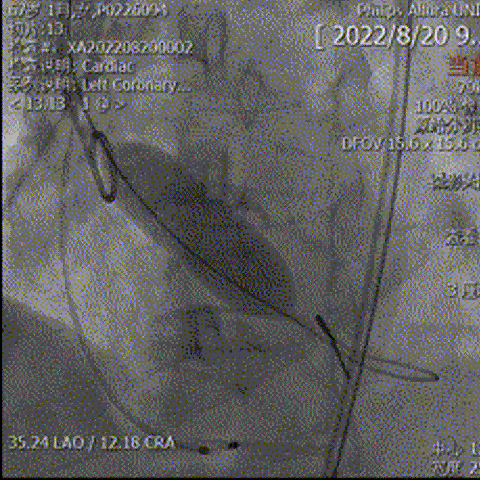

术前CT评估

• Type1型二叶式主动脉瓣,瓣叶增厚伴中重度钙化,左右窦间可见钙化融合嵴;LVOT呈类直筒型;

• 左冠脉开口高度较低,右冠脉开口高度尚可,切线位左冠瓣叶长度>冠脉开口到瓣叶附着缘距离;左冠脉可见少量钙化;

• 瓦氏窦、窦管交界内径偏小、升主动脉内径可;左室腔内径偏小,心室壁明显增厚;

• 瓣环平面与水平夹角为48°,主动脉弓弓距及夹角尚可;

瓣上结构测量

冠脉阻挡风险、横位心及左室大小评估